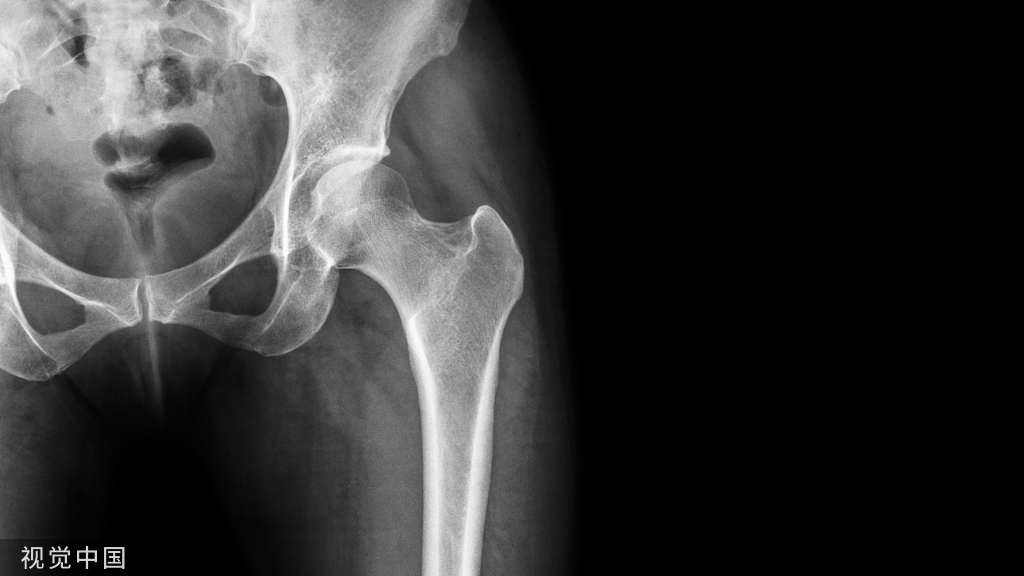

1.股骨头圆韧带窝在髋关节正位片上表现为股骨顶部小半圆形骨质缺损,在旋转屈曲位时表现为股骨头中心部有小空洞(图1)。

图1 正常股骨头圆韧带窝A.韧带窝明显,极似骨缺损;B.转动体位后骨质正常